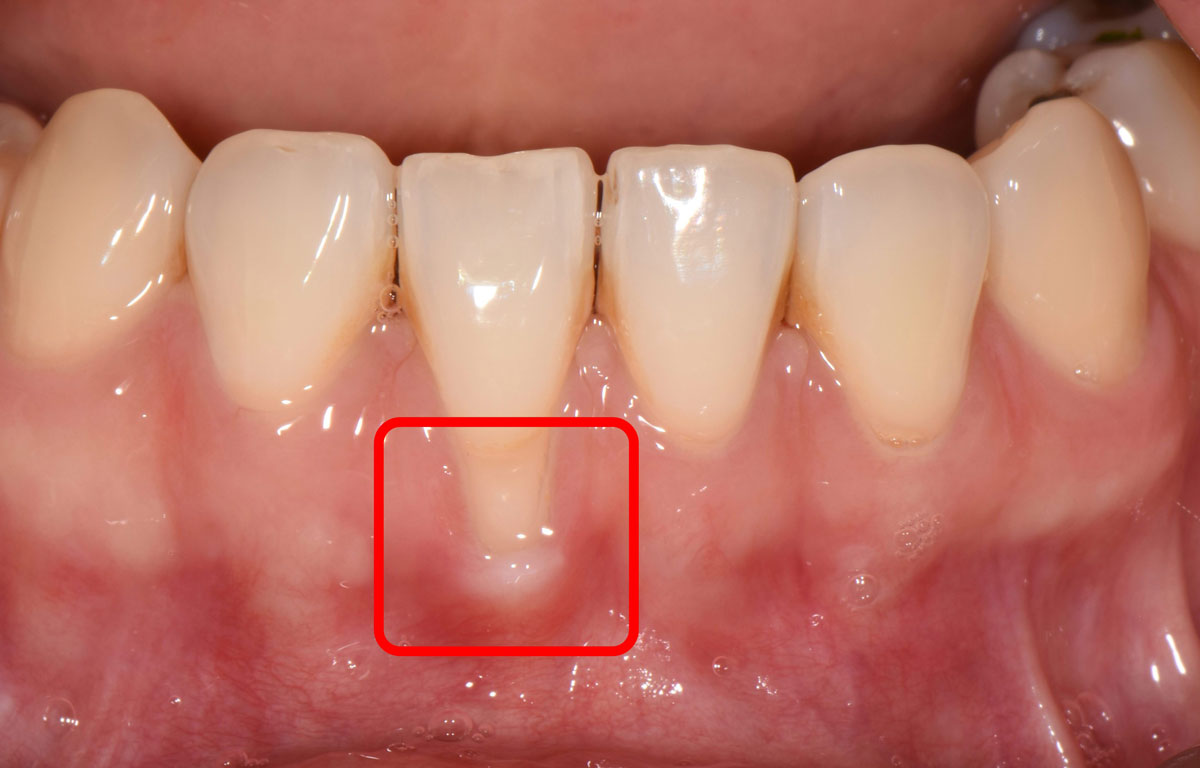

ÀÕ¸öÀÌ Ä¡¾Æ »Ñ¸® ¹æÇâÀ¸·Î ³»·Á°¡¸é Ä¡¾Æ »Ñ¸®°¡ ³ëÃâµÅ Â÷°í ¶ß°Å¿î °Í¿¡ ¹Î°¨ÇØÁø´Ù. Ä¡¾Æ »çÀÌ °ø°£ÀÌ ³Ð¾îÁú °æ¿ì À½½Ä¹°ÀÌ Àß ³¢¸ç, ³ëÃâµÈ ¸éÀ̳ª ÀÎÁ¢ÇÑ ¸é¿¡ ÃæÄ¡°¡ ¹ß»ýÇÒ ¼öµµ ÀÖ´Ù. Æò¼Òº¸´Ù Ä¡¾Æ »çÀÌ¿¡ À½½Ä¹°ÀÌ ¸¹ÀÌ ³¢°Å³ª, ¾Õ´Ï »Ñ¸®°¡ ÀÌÀüº¸´Ù ¸¹ÀÌ º¸À̰í Ä¡¾Æ°¡ ±æ¾îÁø °Íó·³ ´À²¸Áø´Ù¸é ÀÕ¸ö Á¡°ËÀ» ¹Þ¾Æº¼ Çʿ䰡 ÀÖ´Ù.